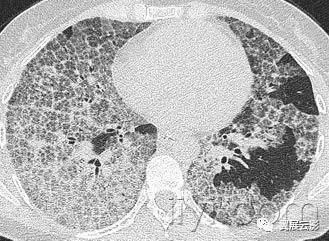

十八、小叶中心性:

解剖:小叶中心性用于描述次级肺小叶的支气管血管束中心区域。病理学上也用这一术语描述终末小支气管远端,位于呼吸性细支气管和肺泡管中心的病变。

CT:正常次级肺小叶中心的点状或者线状的密度增高影,胸膜下25px范围内最明显,代表小叶内的动脉,直径约1mm。

小叶中心性异常包括(1)结节(2)树芽征,提示小气道病变(3)由于临近间质的增厚或者浸润导致小叶中心结果更加清晰(4)小叶中心性肺气肿导致的异常低密度。

附图为小叶中心性肺气肿